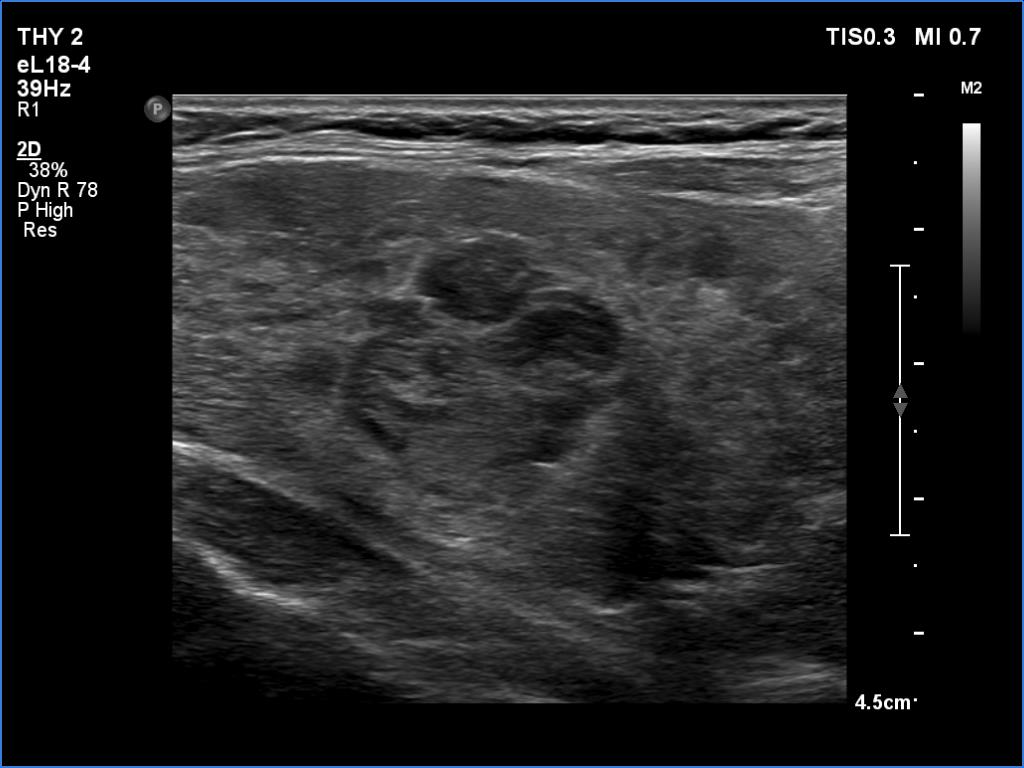

Three years after the first examination (third row of images):

Clinical presentation. The patient has ceased the thyrostatic therapy for six months. Recently, she noticed again complaints suggesting hyperthyroidism.

Palpation: unchanged.

Results of blood tests: hyperthyroidism (TSH undetectable, FT4 39.1 pM/L).

Ultrasonography. There were two changes compared with the previous examination. The thyroid has become echonormal while the lesion in the right lobe has become again hypoechoic.Suggestion: daily 20 mg methimazole. Radioiodine therapy when the FT4 level will become normal.